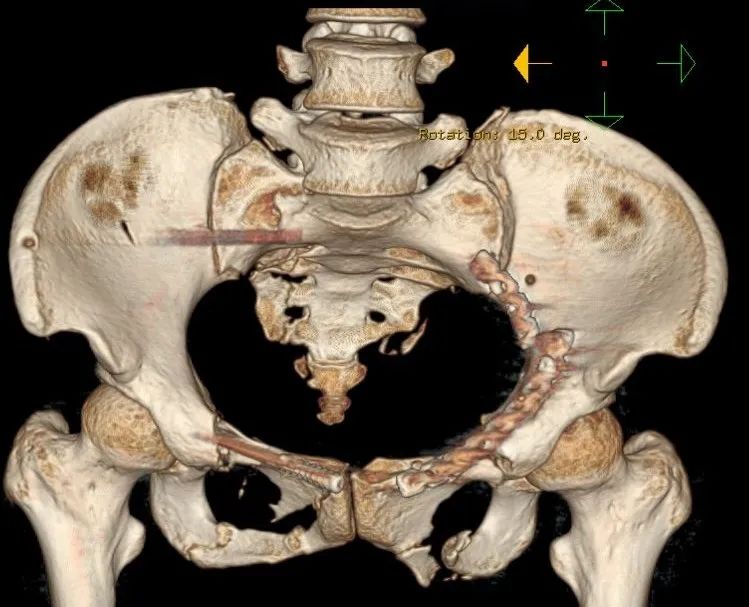

▲CT前位显示骨盆、骶骨多发严重骨折

▲术后骨盆3D影像、正位片